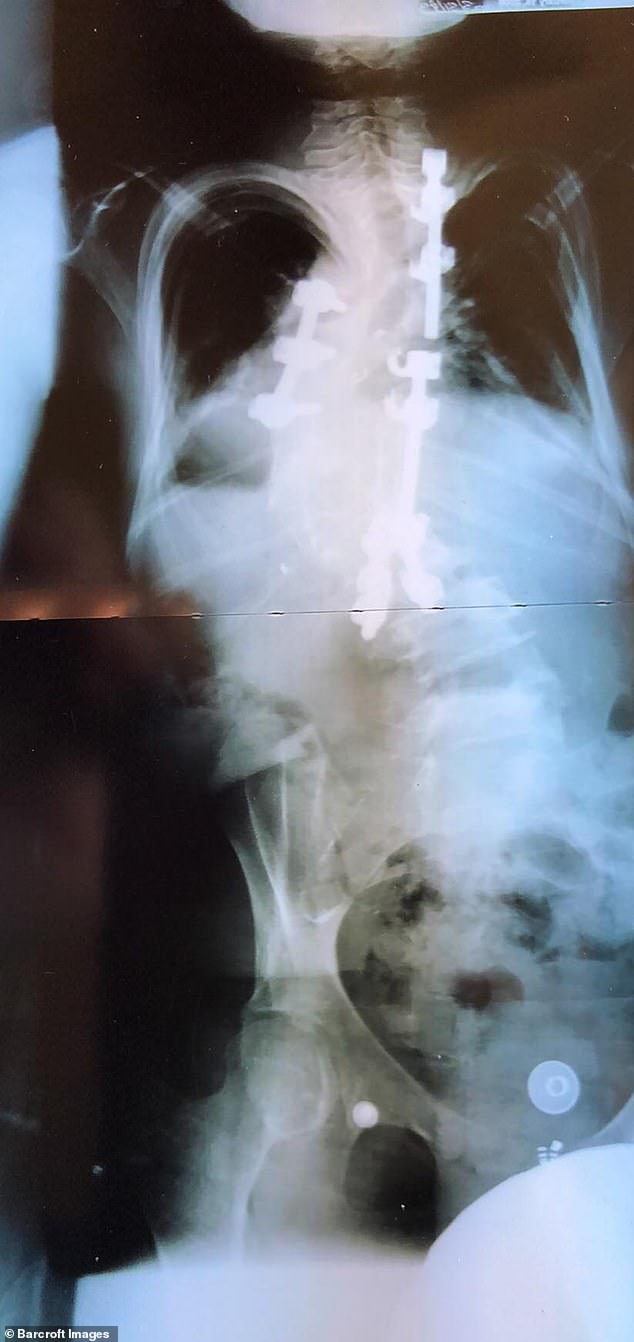

Vanessa Cornelio,25歲,來自亞利桑那州格蘭岱爾市,出生時患有罕見的神經纖維瘤病(NF),導致腫瘤在神經組織上生長。她還被診斷為脊柱側凸,脊柱彎曲、後凸,脊骨向外彎曲,因此脊柱像四歲的孩子。之前Cornelio困擾自己的外表,然而她兩歲的兒子小丹尼爾遺傳了她的神經纖維瘤後,她終於接受了自己的容貌。她説,我不想讓我的兒子看到他媽媽垂頭喪氣。